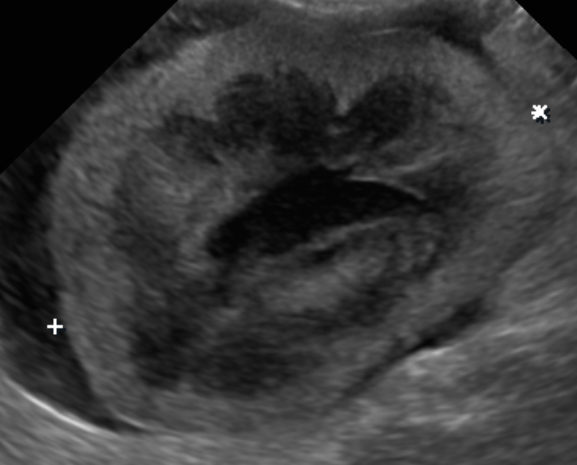

• 貓咪腎臟病 腎臟腫瘤 貓淋巴癌化療

貓咪腎臟病 腎臟腫瘤 貓淋巴癌化療